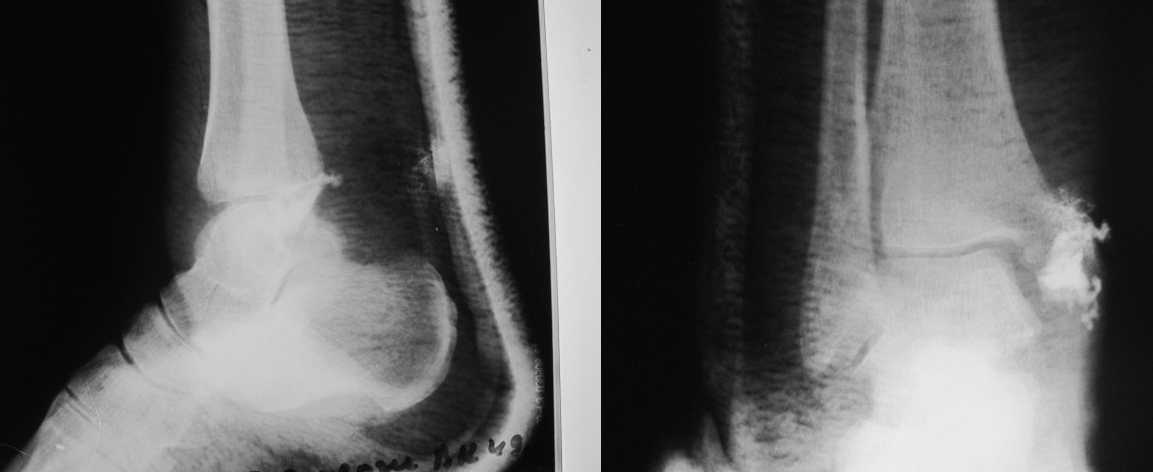

Совершенно верно был такой Пациент парень 29 лет. Только не 2 года а 4 года назад. Лечение растянулось на 2 этапа. На момент сообщения наложил окончатую гипсовую повязку, мазевые повязки, грануляции, закрыл свободной кожной пластикой. Через 2 месяца рана закрылась рубцом, гипс снял отправил на ЛФК. В течение года появлялся дважды - все ОК, нестабильности в суставе не было. Пациент работник УВД - его даже не комисовали. Обратился через 2 года после повторной травмы (опять мотоцикл) - открылся свищ в области медиальной лодыжки. Проведена операция - санация, рубец иссечен, пластика суральным лоскутом - состоятельная. Аппарат Илизарова на 2 месяца. Аппарат демонтировали опять ЛФК - Нестабильности в суставе нет, до сих пор трудится в органах... Опять подумывает о покупке мотоцикла.

К сожалению снимки нашел только после пластики. Р-гр где-то утерял посмотрю не работе.

Нашел в архиве форума снимки от 2007 года. Классная штука интернет! Александру Николаевичу отдельное спасибо!